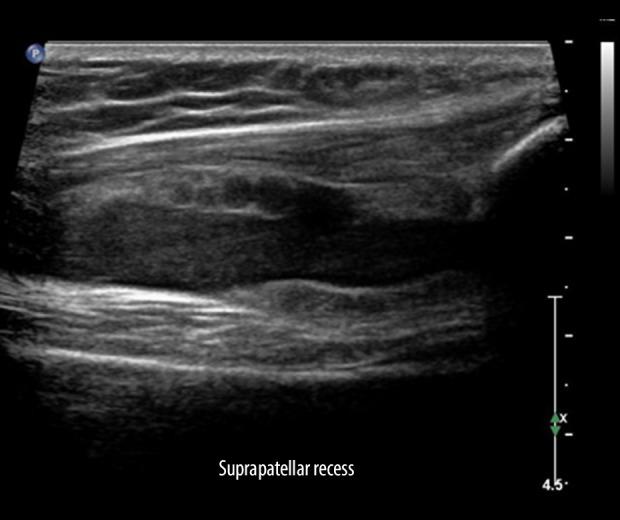

Medical imaging tests are widely used to diagnose a broad spectrum of lower-limb injuries. Among these modalities, ultrasound (US) imaging has gained significant traction as a valuable diagnostic instrument for assessing conditions primarily affecting muscles, tendons, ligaments, and other soft tissues. However, there are important dilemmas related to the indications and possibilities of US in lower-limb injuries. Conflicting findings and approaches raise questions regarding the validity, accuracy, and usefulness of the US in that area. This narrative review attempts to summarize the current state of knowledge regarding US imaging of lower-limb injuries. The study provides a detailed discussion of the existing literature and contemporary insights on the diagnosis of lower-limb injuries using US examination, and draws attention to the role of the US in interventional procedures and monitoring of the healing process. The characteristics of normal muscles, tendons, and ligaments in US imaging are presented, along with the most commonly documented conditions affecting these tissues. Furthermore, the benefits and justifications for employing US in interventional procedures are discussed, ranging from platelet-rich plasma injections to physiotherapeutic treatments like percutaneous electrolysis. The study was further augmented with US pictures depicting various lower-limb injuries, mainly affecting young athletes. This article aims to review the role of US imaging in the diagnosis and management of common lower-limb injuries.

医学影像学检查广泛用于诊断各种下肢损伤。在这些方法中,超声(US)成像作为一种评估主要影响肌肉、肌腱、韧带和其他软组织的疾病的有价值的诊断工具,已经得到了广泛的应用。然而,US 在下肢损伤中的适应证和可能性存在一些重要的难题。相互矛盾的发现和方法使得 US 在该领域的有效性、准确性和实用性受到质疑。本叙述性综述旨在总结目前关于 US 成像在下肢损伤中的应用的知识状况。该研究详细讨论了现有的文献和关于使用 US 检查诊断下肢损伤的最新观点,并提请注意 US 在介入程序和愈合过程监测中的作用。本文介绍了 US 成像中正常肌肉、肌腱和韧带的特征,以及最常见的影响这些组织的疾病。此外,还讨论了 US 在介入程序中的应用的益处和理由,从富含血小板的血浆注射到经皮电解等物理治疗。本文还进一步增加了描述各种下肢损伤的 US 图片,主要影响年轻运动员。本文旨在综述 US 成像在常见下肢损伤的诊断和治疗中的作用。